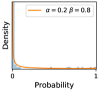

5.1 Distribution of Uncertainty Scores

Distribution of Uncertainty Scores Across Different Severity Levels As explained in Section 3, each uncertainty metric essentially defines an order/ranking among the data points. We conducted an analysis to better understand what data will be assigned high uncertainty under a particular uncertainty metric . Picking out the highest ranked data points (), we calculated the ratio of data points from each SL. Figure 4 summarizes the results as box plots for the Kaggle-DR and the Messidor-2 datasets; additional detailed statistics can be found in Table S.1 in the supplementary materials. From the plot and table, SL1 & SL2 examples account for a higher proportion among the top-ranked uncertain examples across the three ensemble methods. This finding matches our intuition that incipient disease examples (SL1 & SL2) are more likely to be considered uncertain by ensemble methods due to their ambiguity.

5.2 Identifying False Negative Decisions Using Prediction Uncertainties

False Negatives vs. Uncertain Negatives As discussed in Section 2, the FNP measures the probability of the identified uncertain negatives being actual false negatives. The higher the FNP, the more wrong predictions an uncertainty-informed scheme can potentially correct. In Figures 3b, we report the FNP values under different settings from different combinations of ensemble methods and uncertainty metrics. The results in uncertain false negatives and their ratios to the number of uncertain negatives are illustrated in Figures 3a & 3b, respectively. mean gives higher false negative precision values than var, which validates Theorem 1.

A Hypothetical Uncertainty Metric mean+var We can observe from the results in Figures 3 & 4 that the performance indices given by mean and var are sometimes close. Hence, a natural question to ask is how much overlap is there between the uncertain examples identified by the two uncertainty metrics. To answer this question, we created a hypothetical metric mean+var in our analysis in addition to mean and var. The uncertain examples identified by mean+var are the union of the two sets of uncertain examples identified by mean and by var, not subject to the constraint imposed by . Therefore, it is at least as good as mean or var. If mean and var do not have much overlapping, mean+var will identify many more false negatives than either of them alone; however, we can see from Figure 3 that this is not the case. The results given by mean+var do not have much improvement over those given by mean, indicating that many of the false negatives identified by var are also captured by mean, matching the expectation of Theorem 1.

Reduction in the Number of False Negative Decisions Finally, we report the performance of the uncertainty-informed human-AI diagnostic scheme, and compare that to the baseline scheme in which decision uncertainties are not used to inform decision-making. We show in Figure 3c the number of remaining false negatives at different values of , and in Figure 3d the percentage changes w.r.t. the baseline (). We can see from the two plots that mean gives modest improvement compared to var with all three ensemble methods, as asserted by Theorem 1. When , the stacking ensemble method achieved a decrease (1918 people) in the number of false negatives under mean and a decrease (1997 people) under var. We include more detailed results in Tables S.4 & S.5 in the supplementary materials.

Comparing the three ensemble methods in Figure 4, the stacking ensemble method has the highest ratios of SL1 & SL2 data among the high-uncertainty examples it identified under both mean and var. TTA showed slightly better performance than MC-dropout but still falls behind the stacking ensemble method. Considering the fact that SL0 examples accounted for the majority of the dataset, the stacking ensemble method was much more precise (specific) in selecting truly ambiguous data points that were difficult to classify. From Figure 3, we can also see that the stacking ensemble method greatly outperformed the other two methods in finding false negatives under both mean and var uncertainty metrics.

In contrast, the MC-dropout method showed the worst overall performance among the three, as it can be seen from the high ratios of SL0 examples among the uncertain negatives in Figure 4. The histograms in Figure 2 provides another perspective to look into the phenomenon, where a decent proportion of MC-dropout model’s predictions on SL0 inputs entailed low confidence (far from 0 or 1), which from another angle explained why MC-dropout was less specific in terms of lower FNP; many no-DR inputs (i.e. SL0) were erroneously assigned high uncertainty by MC-dropout models.